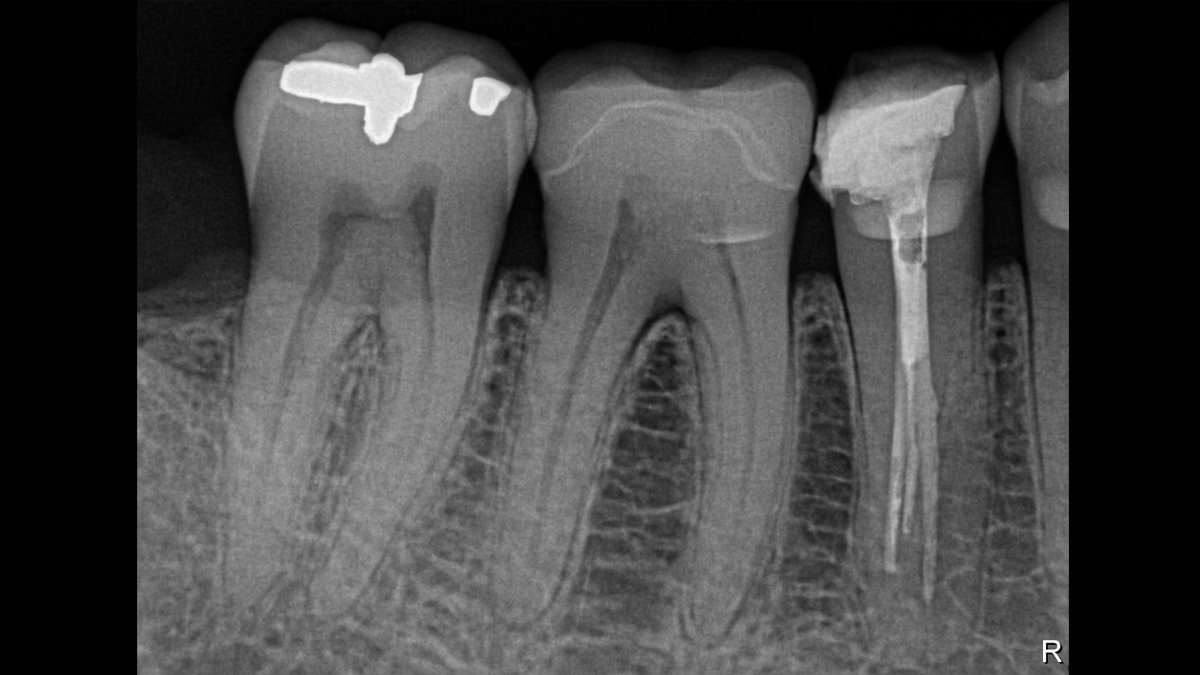

Working with Schick 33: Filtering enhancements

With Schick 33 sensors you have the option of five different filtering options: General Dentistry, Endodontics, Periodontics, Restorative and Hygiene. These clinically specific views are designed to optimize your diagnosis, enhancing the image to suit your needs.

Schick 33 - Gallery of Sample Images